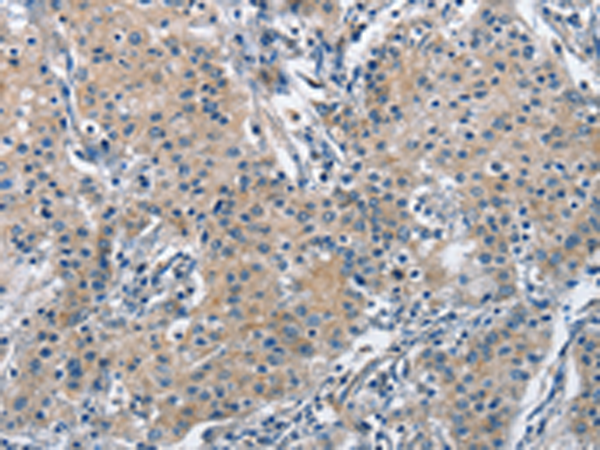

分类: 科研抗体货号: P07997别名: DFNB98; TSP-EAR; C21orf29应用: IHC反应种属: Human